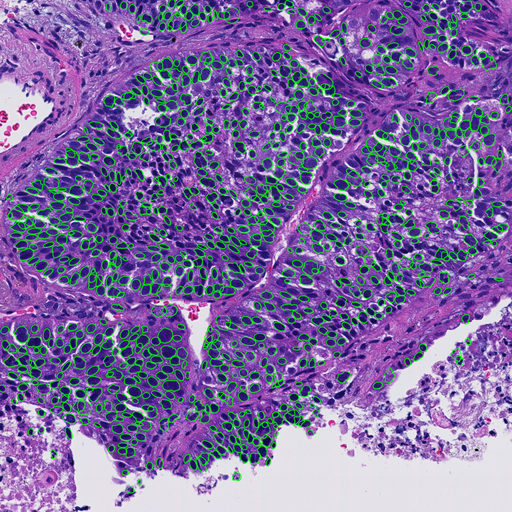

Whole slide images of hematoxylin and eosin (H&E) stained slides collected from 94 non-small cell lung cancer (NSCLC) cases were captured by a virtual slide scanner (NanoZoomer, Hamamatsu Photonics, Japan). Sampling methods were needle biopsy (59 cases), operation (12 cases) and endobronchial ultrasound-guided transbronchial needle aspiration (EBUS-TBNA) (29 cases). Regions of interest (ROI) were selected by an experienced pathologist. After selecting tumor cells only by AI-based tumor cell detecter (Figure.1), following morphological features were calculated: nuclear area, perimeter (Peri), circularity (Circ) and five texture features, i.e., angular secondary moment (ASM), contrast(Cont), homogeneity (Hom) and entropy (Ent) of gray level co-occurrence matrix (GLCM), and contour complexity (CC).